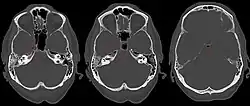

Computertomographie einer Petrositis. Man erkennt als Komplikation Gas (schwarze Flecken) im angrenzenden Schädelinneren

Das Gradenigo-Syndrom (Syn. Lannois-Gradenigo-Syndrom, Pyramidenspitzensyndrom, englisch Gradenigo’s triad) ist Folge einer infektiösen Entzündung der Zellen der Felsenbeinpyramide (Petrositis). Das Syndrom ist eine seltene Komplikation der akuten Mittelohrentzündung. Greift die Entzündung ins Schädelinnere über, verursacht sie durch ein kollaterales Ödem oder entzündliche Infiltration eine Schädigung der benachbarten Hirnnerven mit folgenden Symptomen (Gradenigo-Trias):